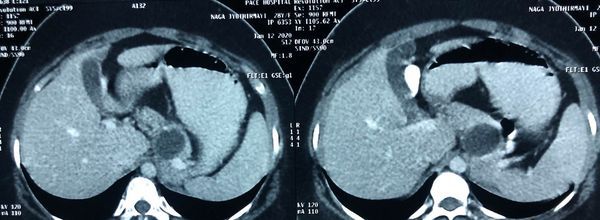

With chemotherapy improved survival with quality of life for Stage 4 cancer patient

Interesting Images March 2019 : Patient came with an early stage carcinoma rectum, underwent Hemicolectomy surgery then lost to follow-up. Later after 9 month patients presented to us with Stage 4 disease (Carcinoma colon with Liver secondaries). Then we started her on treatment with Chemotherapy along with Monoclonal antibodies with six cycle of above said treatment patient achieved near complete remission. We could achieve very good results with chemotherapy even in patients with Stage 4 disease (Carcinoma colon with Liver secondaries).